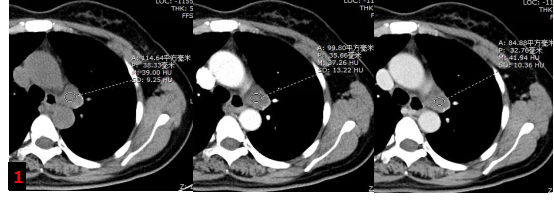

胸部強化CT?

主動脈弓左旁不規(guī)則混雜密度腫塊影,增強未見明顯強化,考慮腫大淋巴結,轉移灶?(圖1)